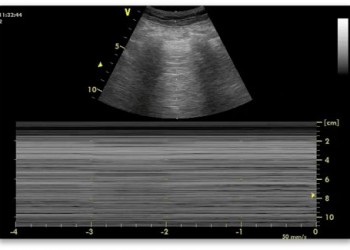

Bu alternatif üstbilişsel müdahale, birinci doktoru analiz moduna (Sistem 1’den Sistem 2’ye) yönlendirir. Hastanın yakın zamandaki cerrahi öyküsünü, USG’deki D-Shape görünümünü, EKG’deki sağ aks sapmasını ve alt ekstremitedeki DVT bulgusunu fark eder. Tanı KOAH değil, Pulmoner Emboli‘dir. Eğer metakognitif denetim mekanizması en baştan çalışsaydı (başka ne olabilir sorusunu primer doktor kendine sorabilirdi), “Sabitleme Hatasına” (Anchoring Bias) düşmeyebilirdi.